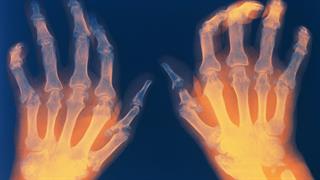

Νέες, προηγμένες απεικονιστικές μέθοδοι παρέχουν ακριβή και έγκαιρη διάγνωση, ευκρινέστερη εικόνα, καλύτερη κατανόηση των παθολογικών ευρημάτων, καθώς και την δυνατότητα χρήσης Τεχνητής Νοημοσύνης στη διάγνωση των ρευματικών παθήσεων. Παράλληλα, μελλοντικές θεραπευτικές παρεμβάσεις υπόσχονται αποτελεσματικότερη αντιμετώπισή τους.

- Η φωτοακουστική απεικόνιση, μια αναδυόμενη βιοϊατρική τεχνική που συνδυάζει τα πλεονεκτήματα της οπτικής και της υπερηχογραφικής απεικόνισης, επιτρέποντας τη δημιουργία εικόνων, τόσο με οπτική ανάλυση όσο και με βάθος ακουστικής διείσδυσης.

- Το PET CT, τεχνική πυρηνικής ιατρικής, με συνδυασμό λειτουργικής και ανατομικής απεικόνισης.

- Η ολοσωματική MRI: Απεικόνιση μαγνητικής τομογραφίας ολόκληρου σώματος, πολλά υποσχόμενο εργαλείο για την αξιολόγηση της συχνότητας και της κατανομής των φλεγμονωδών βλαβών σε ολόκληρο τον αξονικό σκελετό.